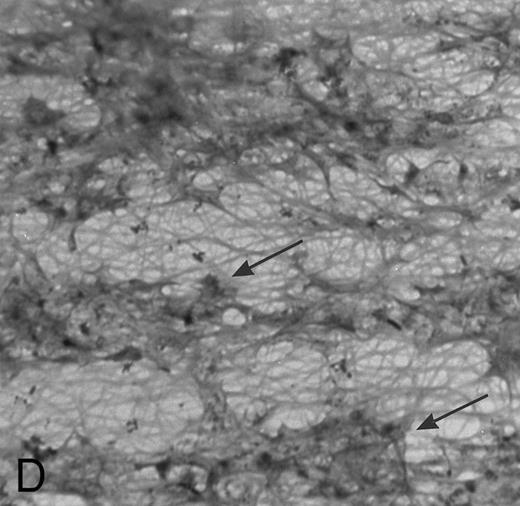

(A) Fibrin network formed under static conditions (Fb-static). Tissue factor–rich ECM-coated coverslips were incubated with PPP in a 6-well plate (10 minutes at 37°C). Arrows indicate neutrophils that have adhered after a perfusion with purified resting neutrophils. (B) Fibrin network formed at low shear. ECM-coated cover slips were perfused with PPP from heparinized blood at shear stress 20 mPa (10 minutes at 37°C). (C) Fibrin network formed at high shear stress. ECM-coated cover slips were perfused with PPP from heparinized blood at a shear stress of 80 mPa (10 minutes at 37°C). (D) Fibrin network with platelets (Fb + platelets). ECM-coated cover slips were perfused twice: first with PPP from heparinized blood at a shear stress of 20 mPa (10 minutes at 37°C), followed by perfusion with citrated whole blood for 7 minutes at a shear rate of 1,600 s−1 (ie, a shear stress of ∼7 Pa). As a result, platelets covered 30% to 40% of the fibrin network (arrows).

Fb + platelets.ECM cover slips were perfused twice to obtain a surface with a fibrin network together with platelets: a first perfusion was performed with PPP as described, followed by a perfusion with citrated whole blood. As a result, platelets adhered to the fibrin network covering 30% to 40% of the total surface (Fig 1D).

PMN Adhesion to Fibrin and Platelets

A fibrin network formed under flow conditions has the unique feature of thick fibers orientated parallel to the flow direction and few unpolymerized fibrin(ogen) monomers (Fig 1C). Since fibrin structure was suggested to influence cellular adhesion,5,24 25 we examined the role of fibrin structure on PMN adhesion at different shear stresses. Tissue factor–rich ECM was exposed to PPP under flow conditions (at shear 20 mPa, Fb-flow) and under static conditions (Fb-static). Both surfaces were subsequently perfused with isolated PMNs at shear stresses 80, 200, and 320 mPa. At shear stresses of 200 and 320 mPa, Fb-flow induced twofold and fivefold more PMN adhesion, respectively, than Fb-static (Table 3). The effect of fibrin fiber alignment on PMN adhesion was examined in more detail. Different shear stresses, ranging from 0 (static) to 80 mPa, were used for fibrin formation on tissue factor–rich ECM. During the static incubation, a fibrin network consisting of randomly distributed fibers was formed (Fig 1A). Fibrin formed under shear conditions (at 1, 20, and 80 mPa) consisted of fibrin fibers that were increasingly aligned along the direction of flow (Fig 1B and C). Figure 3 shows PMN adhesion to these fibrin surfaces after a perfusion at a shear stress of 200 mPa. All fibrin surfaces formed under flow conditions showed increased PMN adhesion compared with Fb-static. Increasing the shear stress during fibrin formation, and thereby the extent of fiber alignment, resulted in increased PMN adhesion. Fibrin formed at a shear stress of 80 mPa showed a threefold increase compared with Fb-static. The orientation of fibrin fibers formed under flow conditions appeared to be important, since a 90° turn of the cover slip coated with fibrin formed at shear stress 80 mPa [Fb-flow (shear 80)] showed no significant increase of PMN adhesion compared with Fb-static (116% ± 26%, n = 8; results not shown).